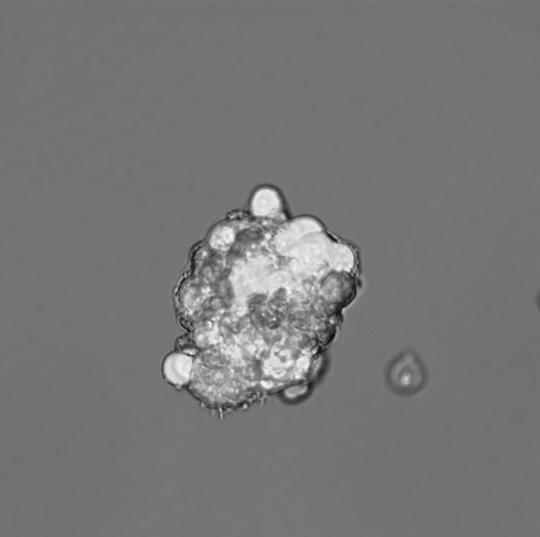

By observing cancer stem cells in a lab setting, they discovered that mitochondria are especially important for the proliferative expansion and survival of cancer stem cells, also known as 'tumour initiating cells', which would then promote treatment resistance.

The research was carried out in breast cancer stem cells grown in a lab, but the theory was also checked against human breast cancer cells from patients. In both cases, proteins within the cells were examined. Sixty-two mitochondrial-related proteins showed significantly increased levels. In particular, fuels such as ketone and L-lactate appeared to be critical, and in the past, they have been shown to accelerate the growth of tumours.